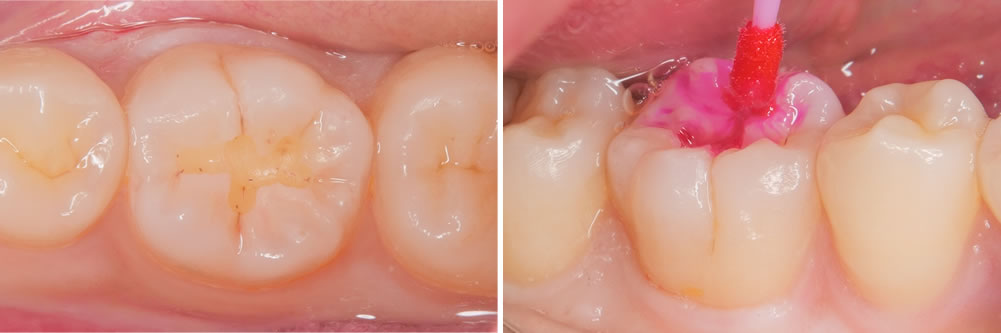

こちらの患者さまは、右下奥歯の虫歯を主訴に来院されました。

右下の奥歯に黒い部分が見受けられます。範囲は小さいため、出来るだけ削らないように先端の小さな器具を用いて丁寧に虫歯を除去していきます。

虫歯治療の除去

う蝕検知液を用いて丁寧に虫歯を取り除いていきます。